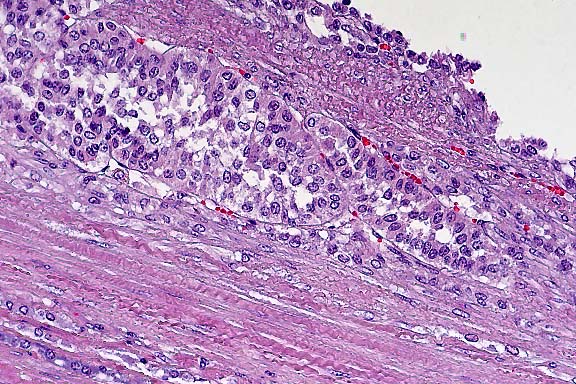

Case 1: Liver. Note focus of coagulative necrosis, mild infiltration of lymphocytes and plasma cells, and scattered hepatocytes containing eosinophilic intranuclear inclusions.(40x obj)

Histologic lesions include gastrointestinal necrosis, hepatocellular necrosis, necrosis and loss of lymphoid tissue, and necrotizing vasculitis. As in this case, eosinophilic intranuclear viral inclusion bodies are present in hepatocytes, biliary epithelium, gastrointestinal epithelium, and lymphoreticular cells associated with these necrotizing lesions. Intranuclear inclusions have also been reported in vascular endothelium. As the contributor observed, some of the esophageal epithelial cells contain eosinophilic intracytoplasmic inclusion bodies. While these inclusions may be poxviral inclusions, conference participants noted that intracytoplasmic herpesviral inclusions have been reported in a natural outbreak of DVE in muscovy ducks.2